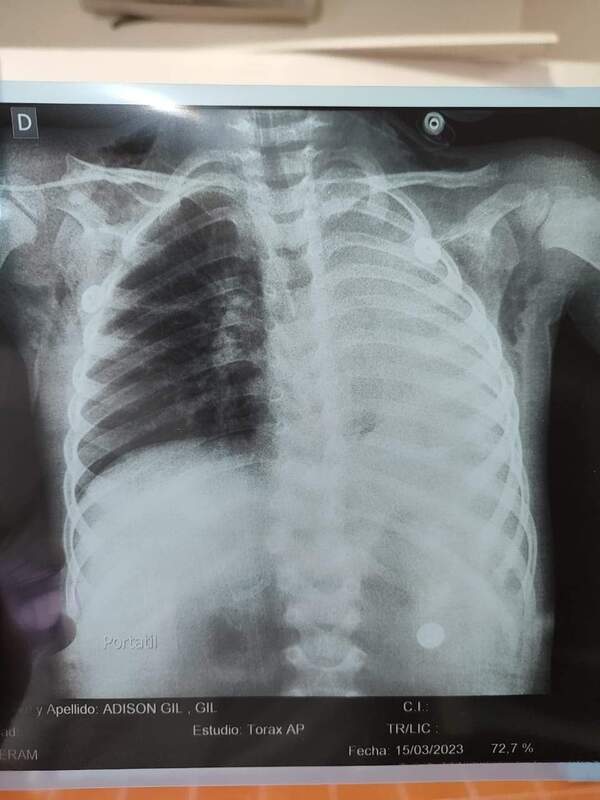

Grano de maíz obstruía vía respiratoria de un niño con chikungunya

Proveniente de Caaguazú, un niño de 3 años de edad, con síntomas de chikunguya y dificultades respiratorias, fue trasladado hasta el Instituto Nacional de Enfermedades Respiratorias y del Ambiente por sus padres para conocer qué realmente lo aquejaba. ...[Leer más]